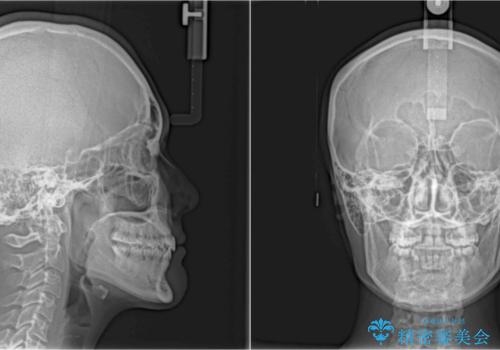

上顎骨の幅が下顎骨よりも小さいので、拡大装置により骨幅を広げて上下関係を改善し、その後インビザラインにて歯並びを整えることとしました。

上下の骨幅を改善したことで、スムーズに歯列矯正を行うことができました。